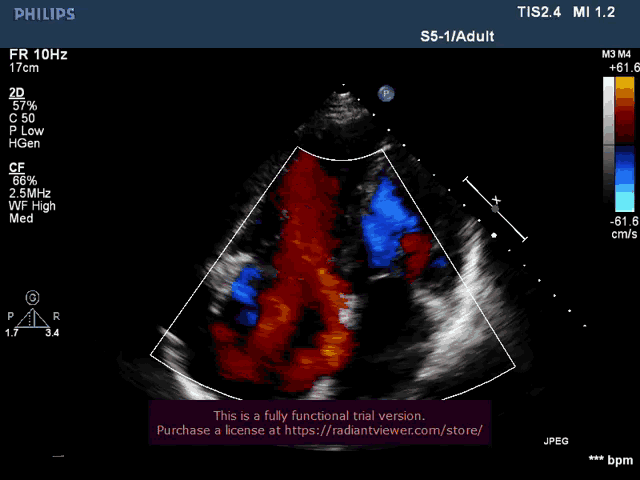

术前心超提示

1. 右房内径增大(上下径x左右径为70x65mm),三尖瓣环值径45x47mm;

2.三尖瓣不增厚,彩色多普勒示重度三尖瓣返流(VCW:10.7x8.1mm);

3.下腔静脉内径增宽为26mm,上腔静脉内径23mm。

术后心超:K-Clip™术后改变,三尖瓣瓣环平面于前后交界处示夹合器回声,瓣叶开放不受限,彩色多普勒示轻度三尖瓣返流(VCW:6.1x3.0mm),连续多普勒估测三尖瓣平均跨瓣压差1mmHg。